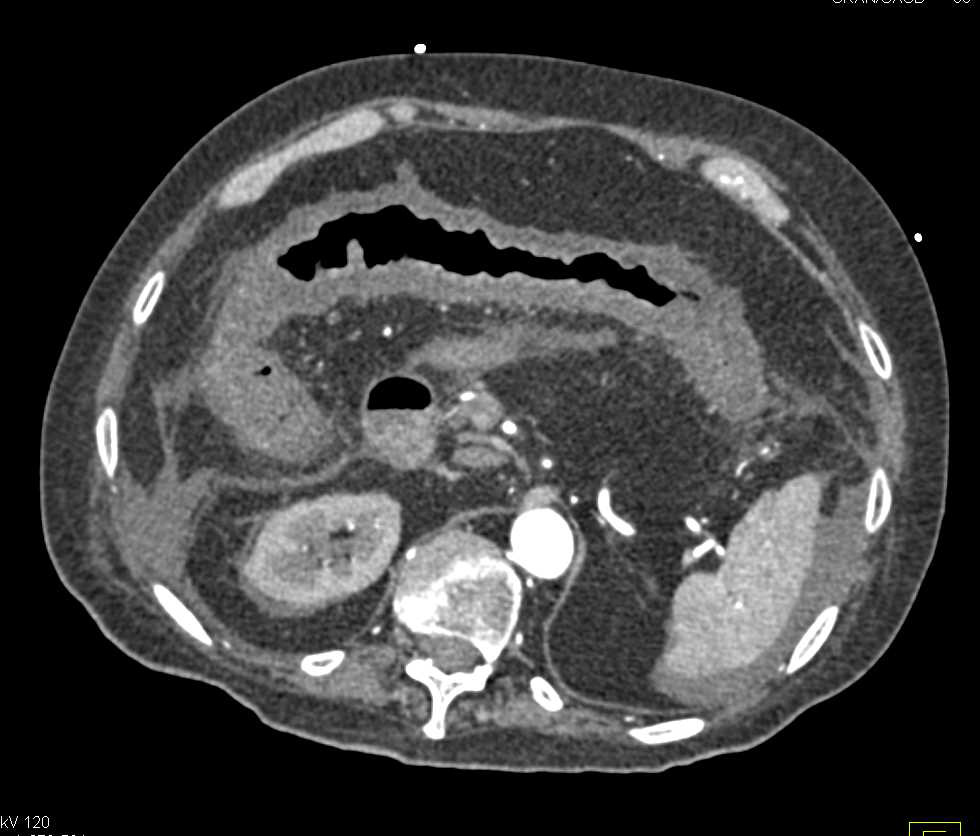

Inflamed Right Colon and Appendix due to Colitis